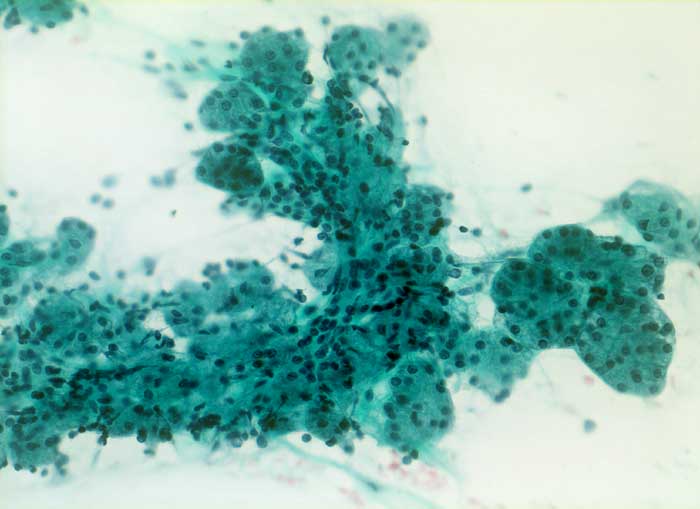

PathoPic ID 5525 - Normale Speicheldrüsenazini

Normale Speicheldrüsenazini

Normalbefund

Parotis

Kopf & Hals, Sinnesorgane

Feinnadelpunktat der Parotis: ganzes Drüsenläppchen mit Azini in traubenförmiger Anordnung.

Zytologie

200